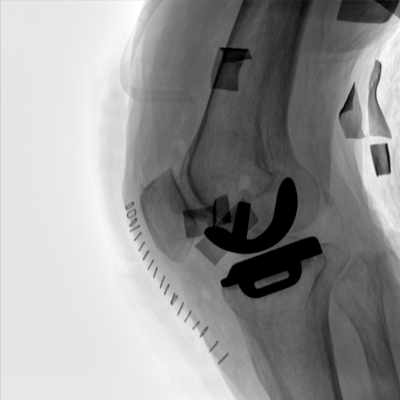

大尺寸動(dòng)態(tài)平板探測器,高DQE、低噪聲、圖像清晰。采用多分辨率圖像增強處理技術(shù),不同部位不同圖像處理算法,滿(mǎn)足客戶(hù)多樣化的需求。

采用智能變頻脈沖透視技術(shù),優(yōu)化圖像質(zhì)量的同時(shí)降低輻射劑量,呵護醫患健康

多角度自由旋轉,滿(mǎn)足患者復雜擺位需求。